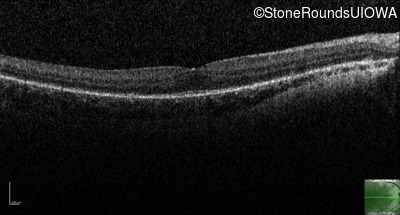

Optical Coherence Tomography - Right - 10/16 sc

Exemplar / OCT Stack

OCT Stack